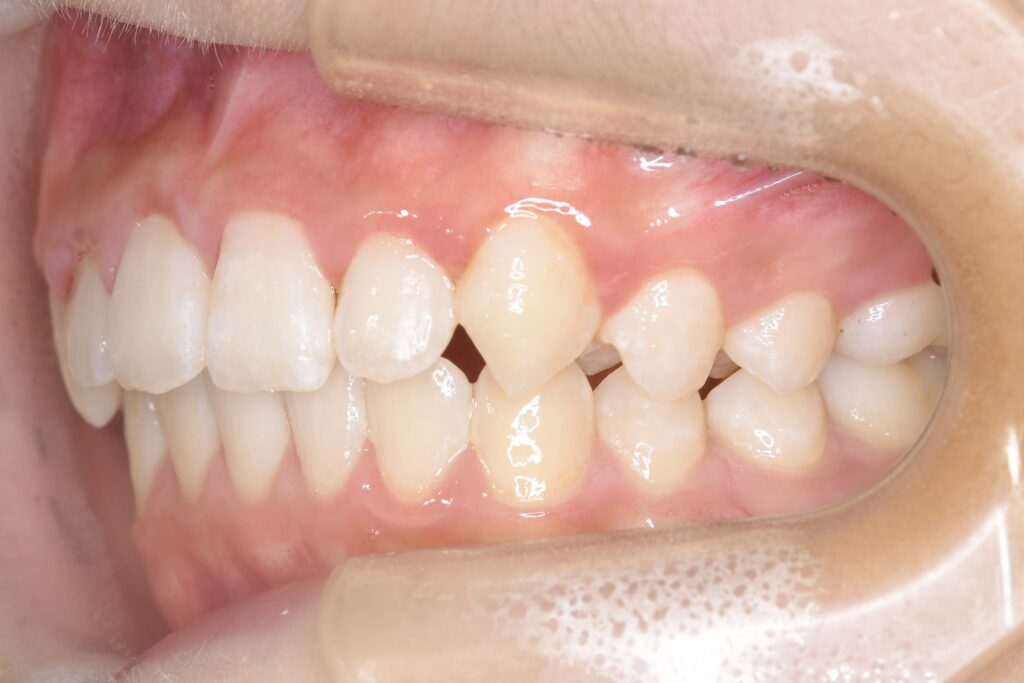

AFTER

主訴 通っている歯医者で矯正した方がいいと言われて気になっている。下の前歯がでこぼこしている。

診断名・主な症状 下顎前歯の叢生を伴う過蓋咬合

治療内容 上下の歯並びの幅を拡げつつ、前歯の関係を改善しました。

通院回数 20回

費用 50万円程度(税別)  29331